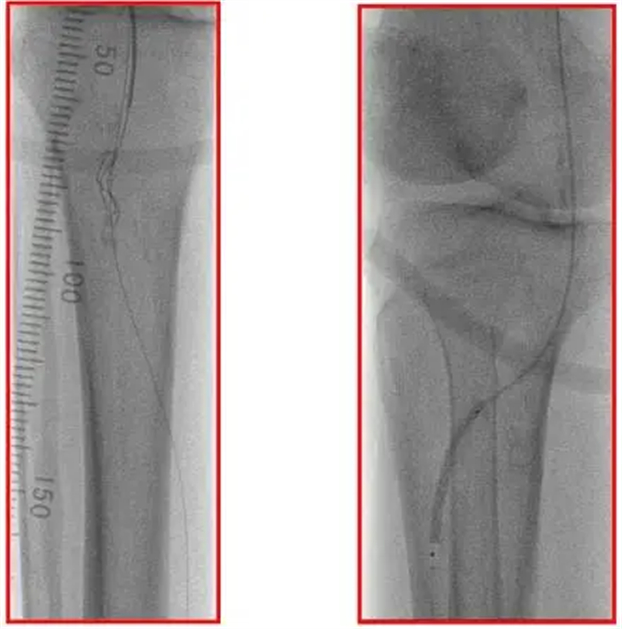

导丝通过,冲击波球囊扩张